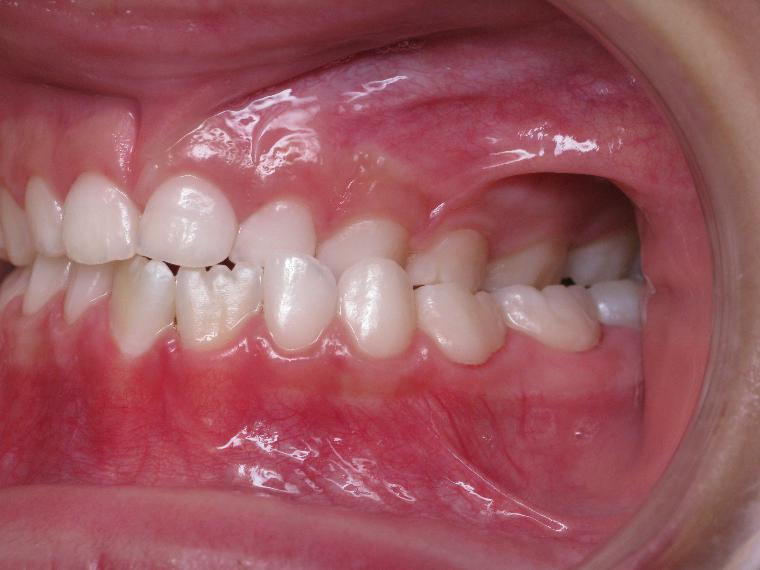

appareillage multibagues pendant 3 ans

surveillance de la dentition par gouttieres nocturne

bilan début et fin de traitement